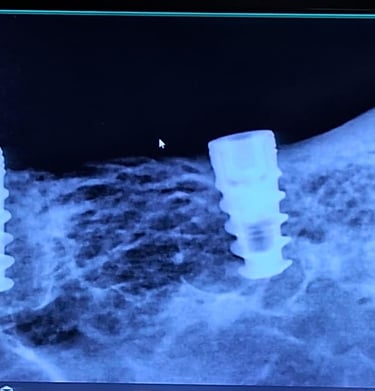

Single Sitting RCT

RCT is done in one visit, usually when the infection isn’t severe. It includes cleaning, shaping, disinfecting, and sealing the canal, followed by final restoration.